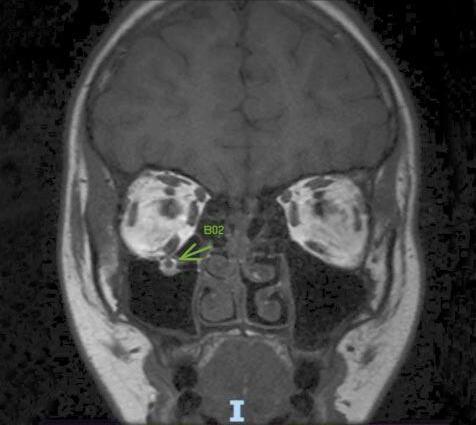

Ante la sospecha diagnóstica de neuritis óptica atípica, solicitamos laboratorio completo con análisis de anticuerpos AQP4 y anti MOG, resonancia magnética de cerebro, órbita y columna cervical, con y sin contraste. El análisis de los anticuerpos solicitados arrojó un resultado negativo para la totalidad.

Para destacar, en la RMN de órbita se apreciaron múltiples hiperintensidades espontáneas proveniente de la sustancia blanca bihemisférica y en la RMN de columna cervical se hallaron imágenes de hiperintensidad focal en T2 de la de hemi médula derecha, extendiéndose a la altura de C4 y C5, de 24 mm diámetro craneocaudal, compatible con lesión desmielinizante inflamatoria.

Se interpretó el cuadro como un trastorno del espectro de la neuromielitis óptica, por lo que se indicó tratamiento inmediato con pulsos de corticoide intravenoso y ante la falta de respuesta a los mismos, se decidió realizar plasmaféresis, con la que, posterior a cinco ciclos, se evidenció una mejoría de la agudeza visual de ambos ojos a 20/25.

Imagen 4: Resonancia magnética de encéfalo y órbitas (con y sin gadolinio). En pulso FLAIR se aprecian múltiples hiperintensidades espontáneas provenientes de la sustancia blanca bihemisférica, la dominante a nivel temporal derecho, de 12 mm de diámetro, sugestivas de lesiones desmielinizantes. No generan efecto de masa y presentan discreto realce.